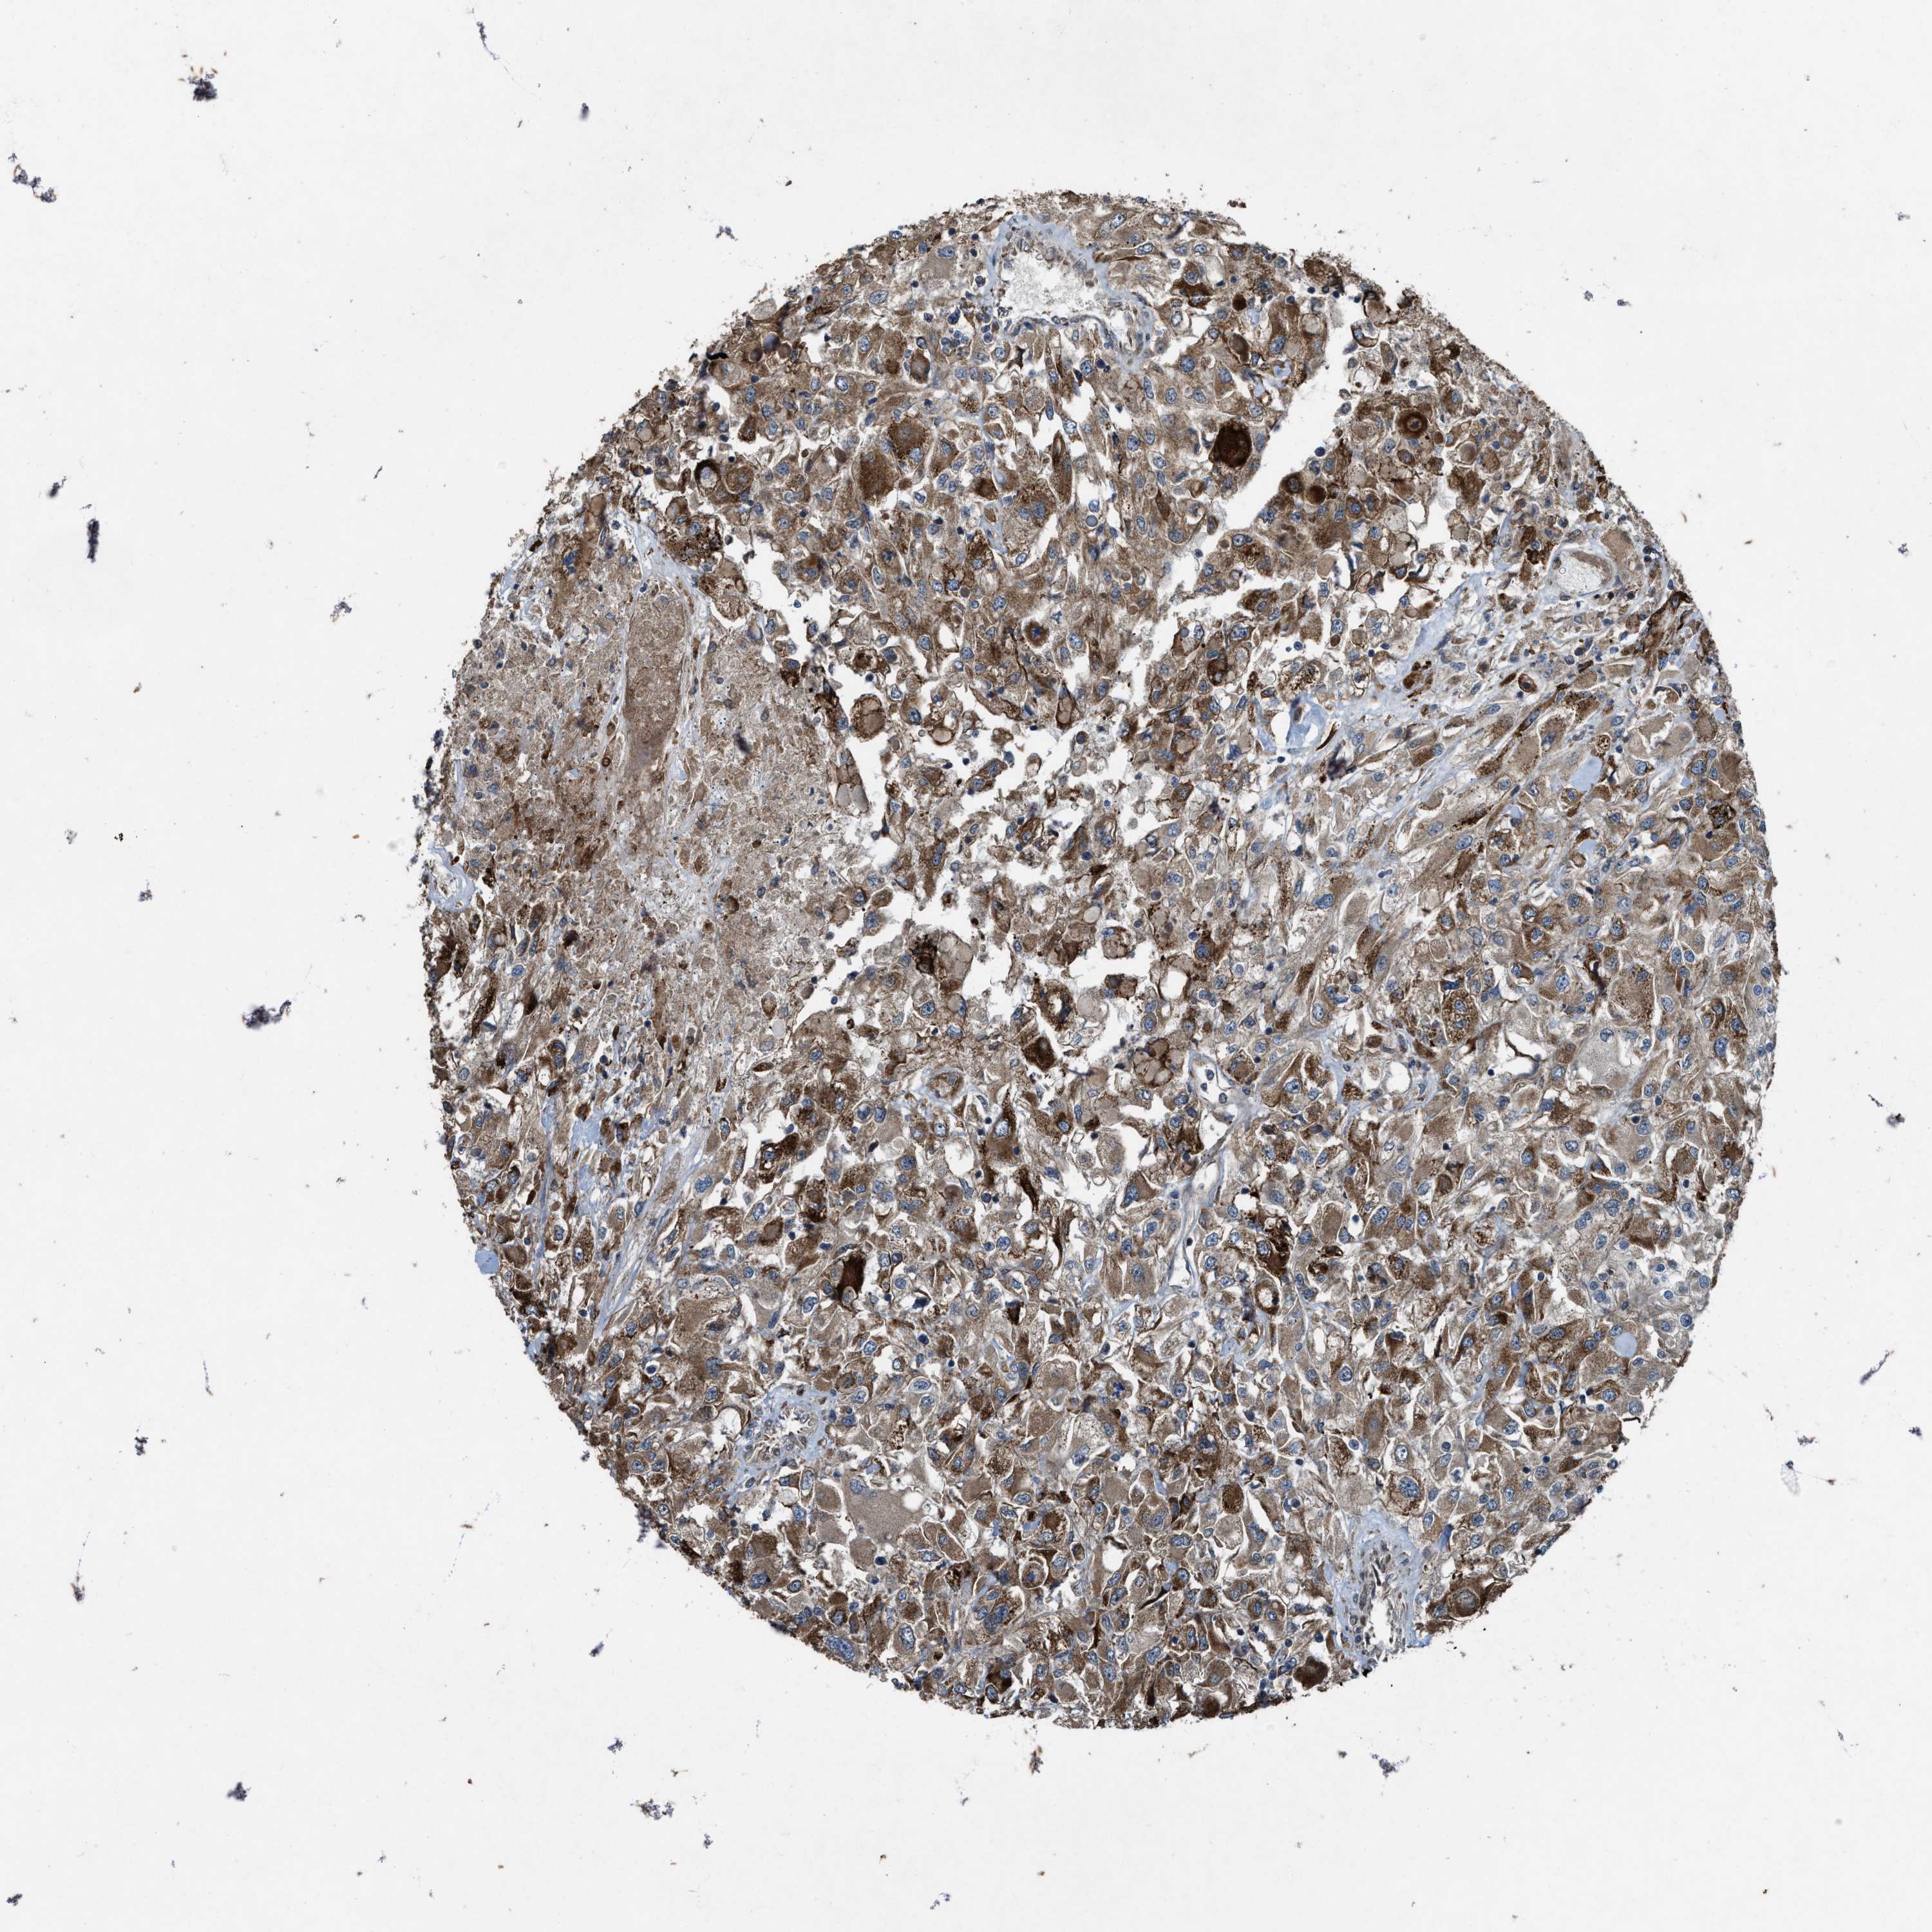

KIDNEY RENAL CLEAR CELL CARCINOMA (TCGA) - Interactive survival scatter ploti

The Survival Scatter plot shows the clinical status (i.e. dead or alive) for all individuals in the patient cohort, based on the same data that underlies the corresponding Kaplan-Meier plots. Patients that are alive at last time for follow-up are shown in blue and patients who have died during the study are shown in red.

The x-axis shows the expression levels (FPKM) of the investigated gene in the tumor tissue at the time of diagnosis. The y-axis shows the follow-up time after diagnosis (years). Both axes are complimented with kernel density curves demonstrating the data density over the axes. The top density plot shows the expression levels (FPKM) distribution among dead (red) and alive patients (blue). The right density plot shows the data density of the survived years of dead patients with high and low expression levels respectively, stratified using the cutoff indicated by the vertical dashed line through the Survival Scatter plot. This cutoff is automatically defined based on the FPKM cutoff that minimizes the p-score. The cutoff can be changed by dragging the vertical line or by entering a cutoff value in the square labeled "Current cut-off".

Under the Survival Scatter plot the p-score landscape (black curve; left axis) is shown together with dead median separation (red curve; right axis). Dead median separation is the difference in median mRNA expression between patients who have died with high and low expression, respectively. It is calculated as follows: median FPKM expression of dead patients with high expression - median FPKM expression of dead patients with low expression. This is intended to aid the user in visually exploring custom cutoffs and the associated p-scores and dead median separation.

Individual patient data is displayed and can be filtered by clicking on one or more of the category buttons on the top of the page. Categories describing expression level and patient information include: high, low, alive, dead, female, male and tumor stages. The scale of the x-axis can be toggled between linear and log-scale by clicking on the "x log" button. Mouse-over function shows TCGA ID, patient information and mRNA expression (FPKM) for each patient.

& Survival analysisi

Kaplan-Meier plots summarize results from analysis of correlation between mRNA expression level and patient survival. Patients were divided based on level of expression into one of the two groups "low" (under cut off) or "high" (over cut off). X-axis shows time for survival (years) and y-axis shows the probability of survival, where 1.0 corresponds to 100 percent.

Survival analysis data not available.

TCGA RNA samplesi

RNA-seq data is reported as average FPKM (number Fragments Per Kilobase of exon per Million reads), generated by the The Cancer Genome Atlas (TCGA) .

Normal distribution across the dataset is visualized with box plots, shown as median and 25th and 75th percentiles. Points are displayed as outliers if they are above or below 1.5 times the interquartile range. FPKM values of the individual samples are presented next to the box plot.

Average pTPM 0.0

Number of samples 521